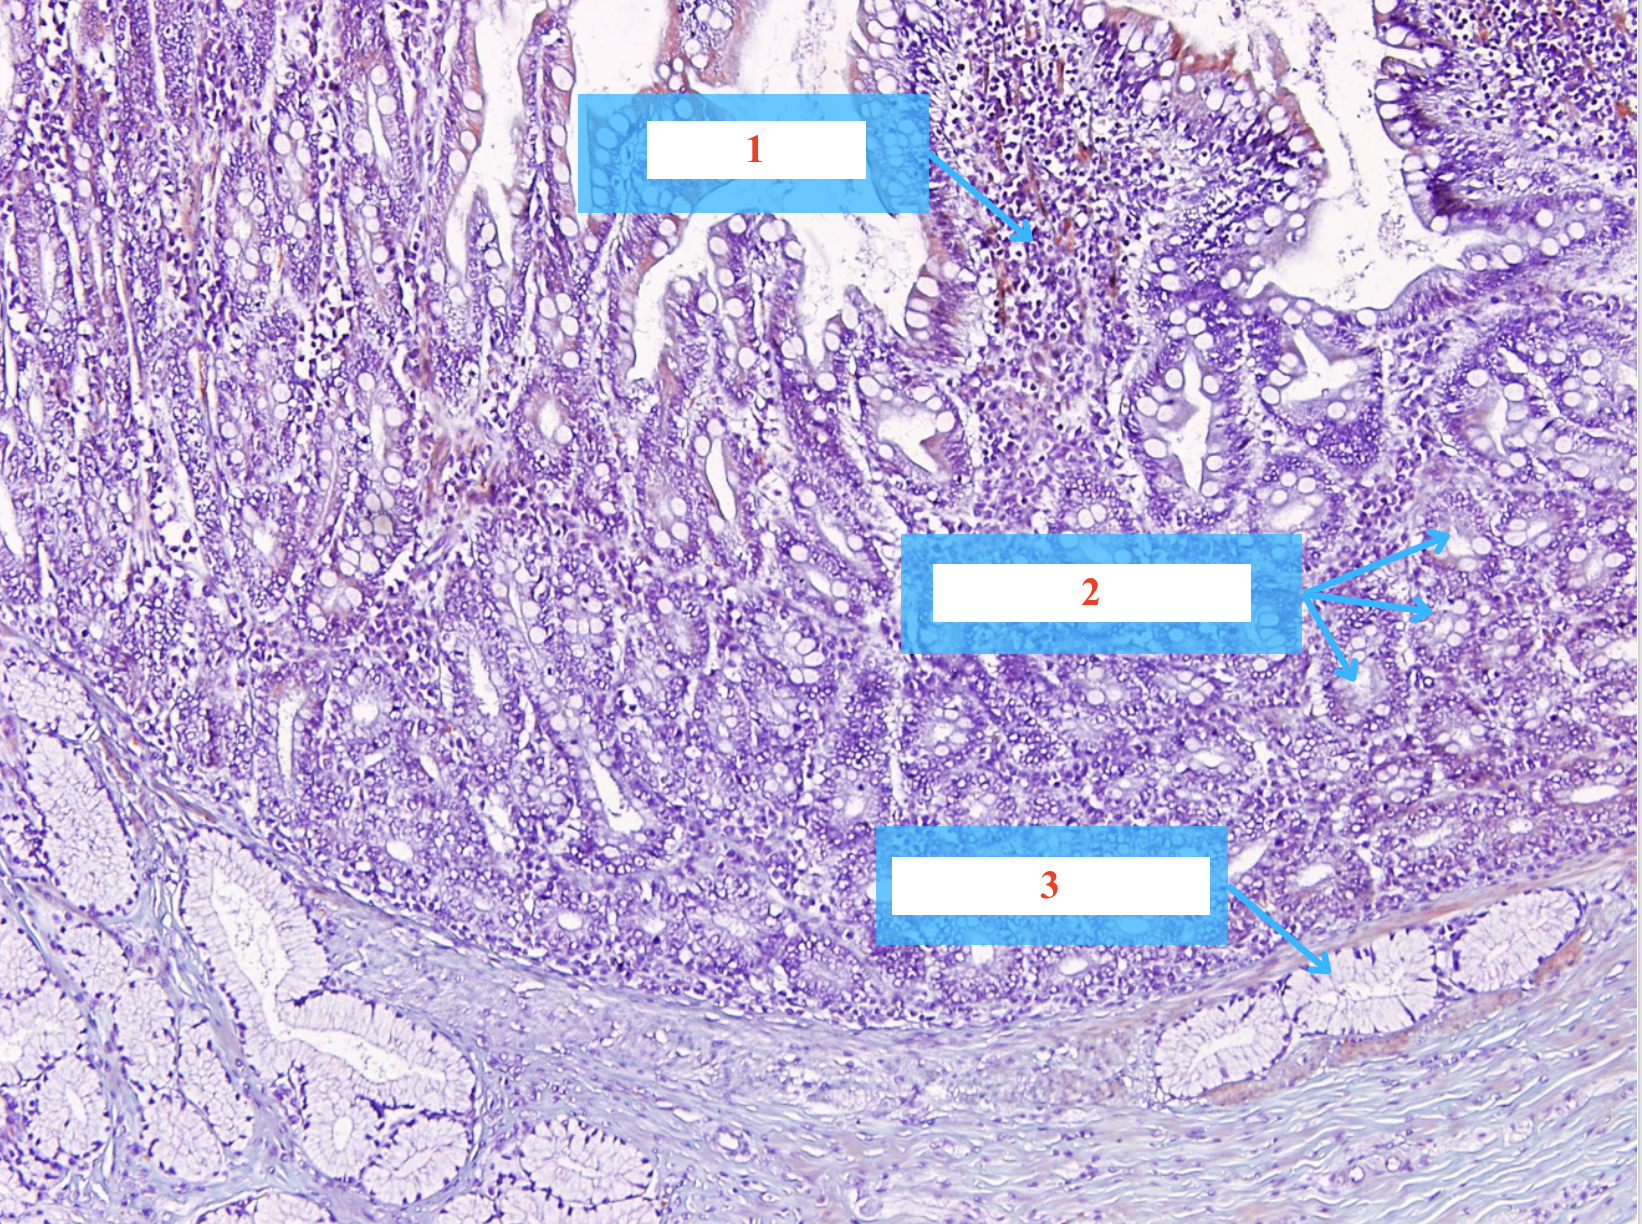

Cấu trúc gì ? - Tiêu bản gì ?

Nhung mao tá tràng

Tuyến Lieberkühn tá tràng

Tuyến Brünner